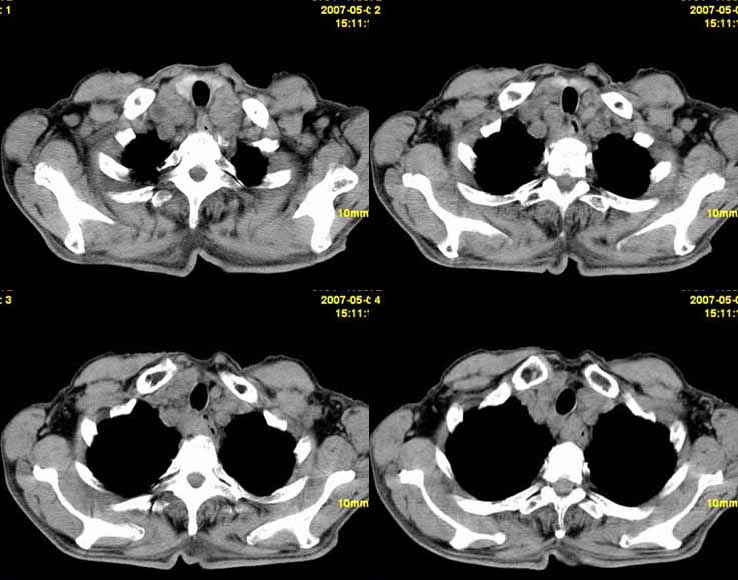

以下是引用小初学者在2007-5-12 11:09:00的发言:[br][br]双肺弥漫性质纤维化(考虑矽肺所致),并发左肺下叶背段周围性肺癌纵隔淋巴转移。

以下是引用zhangzhongshou在2007-5-12 12:09:00的发言:[br]1、左下叶背段周围型肺癌左肺门及纵隔淋巴结转移可能性大。[br]2、弥漫性肺气肿(双侧)。[br]3、双肺间质纤维化。

以下是引用老爱克斯新网客在2007-5-12 12:54:00的发言:[br]1周围型肺癌纵隔肺门淋巴结转移,2肺间质纤维化,